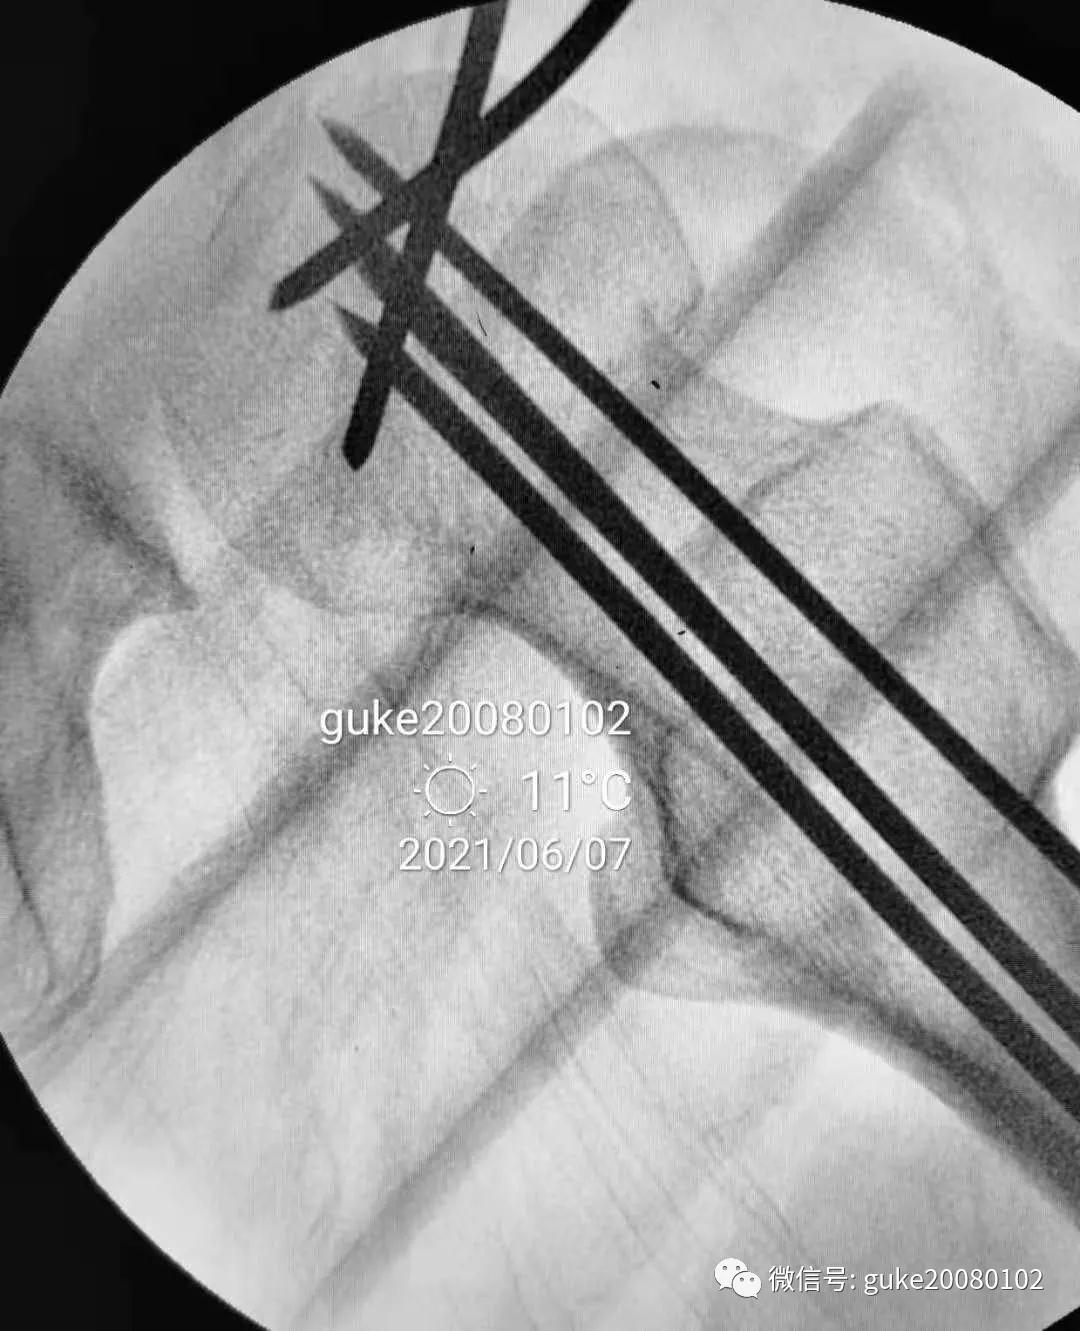

2.外侧植入克氏针一枚,临时固定骨折。

1、植入的第一枚克氏针,前倾和颈干角均满意。将其作为标志针。

2、植入第二枚导针,调整前倾和颈干角。

3、数次调整三枚导针到最合适的位置。